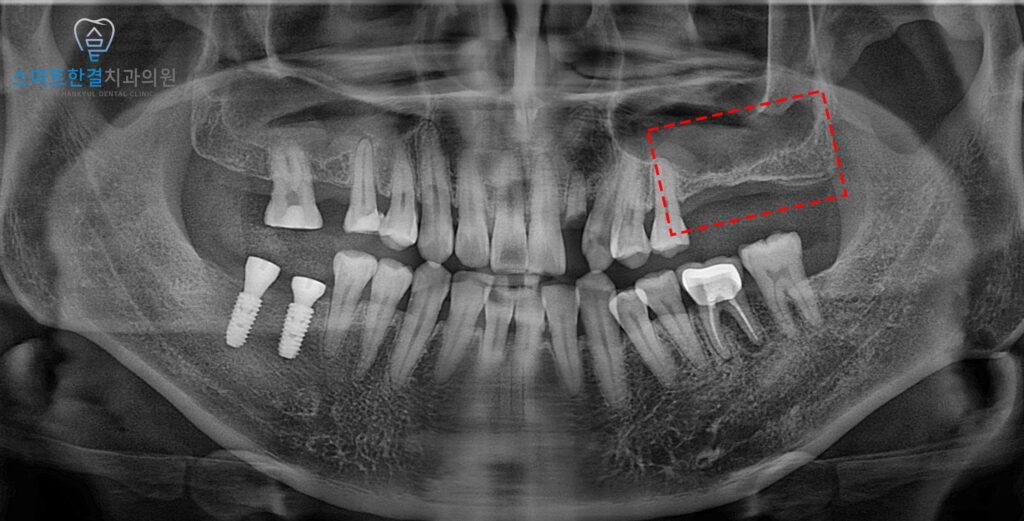

파노라마를 촬영해 확인해 보니,

왼쪽 위 큰 어금니의 상실로 인해

양측으로 식사하기 힘든 상황이었어요.

또한 치아가 오랫동안

없는 상태로 방치되면서,

치조골이 점차 흡수·소실되어

뼈의 높이가 부족한 상황이 되었어요.

이로 인해 임플란트만

바로 식립하기는 어려웠고,

상악동거상술을 통해 부족한 뼈를

보강하는 과정이 필요했는데요.